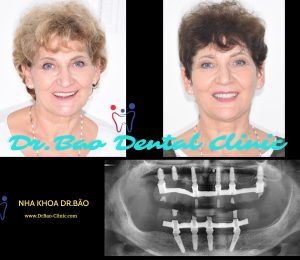

- The fouth stage: full mouth rehalibitation and finish the implant treatment.

The fouth stage: full mouth rehalibitation and finish the implant treatment.

Try-in the temporary crown

The final smile